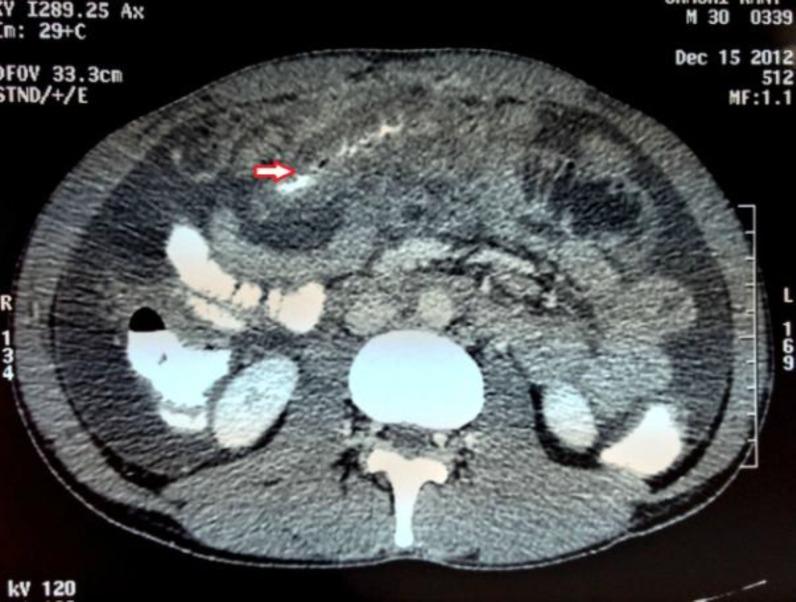

A 30 years old male was admitted to our hospital with the complaints of epigastric pain, vomitting and swelling of his left limb for the past six days. He was also having diarrhea for the last several months. He had been evaluated for chronic diarrhea and ascites before he sought the current consultation. Duplex color doppler of left limb showed DVT of distal calf vein. Contrast enhanced CT imaging of abdomen revealed thickening of duodenum, proximal jejunal wall and presence of ascites. Duodenal biopsy showed normal villous pattern with mild inflammation and eosinophilic infiltration. The constellation of clinical presentation, hypereosinophilia, CT and biopsy findings all is in consistence to EG. The patient was treated with prednisolone 20 mg/day for four weeks and tapered slowly. Acute pancreatitis was managed conservatively while DVT was treated with heparin and oral anticoagulants. The patient's diarrhea settled and ascites resolved completely. At follow up, the absolute eosinophil count was 300/μl and the patient was doing well.